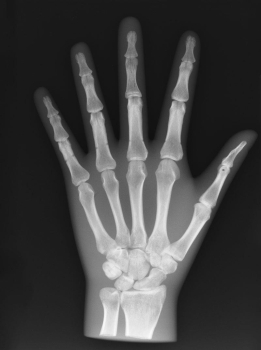

Dieses Röntgen-Teilphantom bietet Ihnen die einmalige Möglichkeit, reale Röntgenaufnahmen so oft Sie wollen zu wiederholen. Das Modell enthält echte menschliche Knochen und erlaubt so, echte Aufnahmen zu machen. Das Modell eignet sich perfekt für Schulen und Ausbildungsstätten, aber natürlich auch für die Medizintechnik, da verschiedene Einstellungen mit dem gleichen Körperteil wieder und wieder ausprobiert werden kann, ohne dass eine Gefährdung des Patienten in Kauf genommen werden muss. Das Modell ist in transparentem Kunststoff fest eingebettet. Diese Ausführung ist mit einem undurchsichtigen Lack versehen, so dass die inneren Strukturen nicht zu erkennen sind. Bei diesem Modell handelt es sich um ein handgefertigtes Einzelstück, das in seiner Größe und Ausführung abweichen kann. Bedingt durch das Fertigungsverfahren können im Innern des Phantoms Verfärbungen oder Risse vorhanden sein, dies ist produktionsbedingt und stellt keinen Defekt dar. Der Verkauf dieses Modells erfolgt nur gegen Nachweis der medizinischen Verwendung.